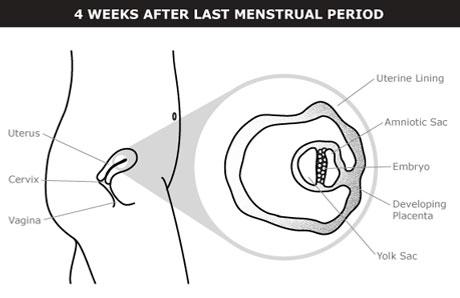

¿Qué sucede en el primer mes de embarazo?

El embarazo se divide en 3 trimestres. Cada trimestre dura poco más de 13 semanas. El primer mes marca el comienzo del primer trimestre.

¿Qué es la edad gestacional?

El tiempo del embarazo se mide usando la “edad gestacional”. La edad gestacional comienza el primer día de tu último periodo menstrual (UPM).

La edad gestacional puede resultar confusa. La mayoría de la gente piensa que el embarazo dura 9 meses. Y es cierto que el estado de embarazo dura unos 9 meses. Pero como el embarazo se mide desde el primer día de tu último periodo menstrual, alrededor de 3 a 4 semanas antes del estado de embarazo propiamente dicho, un embarazo a término por lo general se extiende por unas 40 semanas desde el último periodo menstrual, es decir, casi 10 meses.

Muchas personas no recuerdan exactamente cuándo comenzó el último periodo menstrual, pero no hay nada de qué preocuparse. La manera más segura de determinar la edad gestacional al principio del embarazo es con un ultrasonido.

¿Qué sucede durante las semanas 1 y 2?

Estas son las primeras 2 semanas del ciclo menstrual. Tienes el periodo menstrual. Unas 2 semanas después, el óvulo más maduro se libera del ovario. Esto se denomina ovulación. La ovulación puede ocurrir antes o después, según la duración del ciclo menstrual.

El ciclo menstrual promedio es de 28 días. Una vez liberado, el óvulo recorre la trompa de Falopio hasta llegar al útero. Si el óvulo se encuentra con un espermatozoide, se combinan. Esto se denomina fecundación. Es más probable que se produzca la fecundación si tienes sexo vaginal sin protección durante los 6 días anteriores a la ovulación, incluido el día de la ovulación.

¿Qué sucede durante las semanas 3 y 4?

El óvulo fecundado baja por la trompa de Falopio y se divide en más y más células. Llega al útero unos 3 o 4 días después de la fecundación. Las células divididas forman una bola que flota en el útero durante unos 2 o 3 días.

El embarazo comienza cuando la bola de células se adhiere a la pared del útero. Esto se denomina implantación. Suele comenzar a los 6 días después de la fecundación y tarda de 3 a 4 días en completarse.

No siempre se produce un embarazo, incluso si un espermatozoide fecunda un óvulo. Hasta la mitad de todos los óvulos fecundados se pierde durante el periodo menstrual, antes de completarse la implantación.